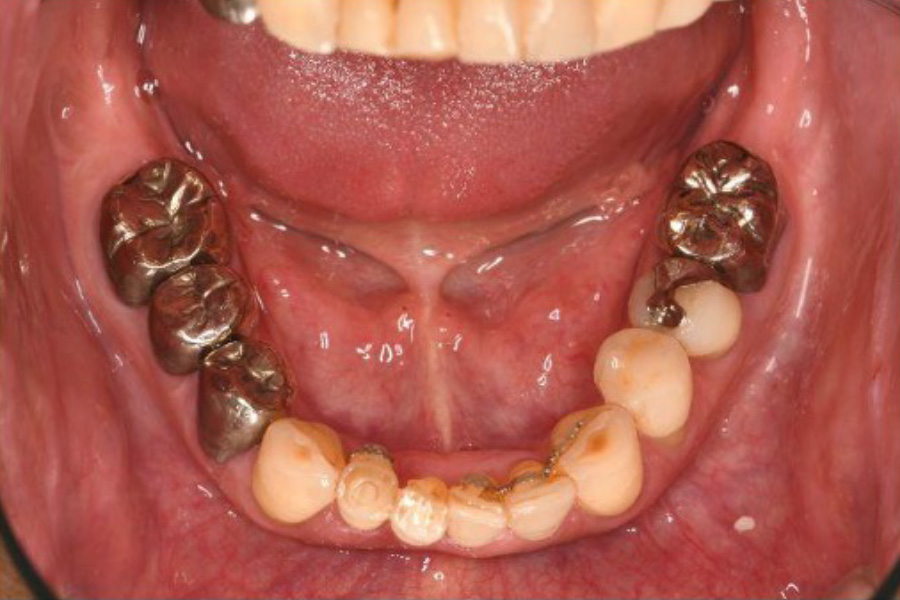

治療前

| 治療内容 | 全顎治療:歯周病治療、抜歯、根管治療、 咬合治療・矯正治療、フルメタルクラウン(保険) |